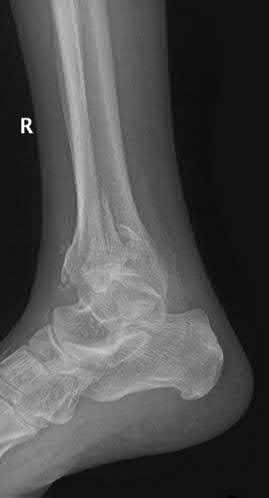

A 28-year-old male sustains a severe hyper-dorsiflexion injury to his ankle in a motor vehicle accident, resulting in a Hawkins Type III talar neck fracture. Which of the following arteries provides the predominant blood supply to the body of the talus, placing it at significant risk for avascular necrosis in this injury?

Explanation

The artery of the tarsal canal, which is a branch of the posterior tibial artery, provides the dominant blood supply to the talar body. In a Hawkins Type III fracture (talar neck fracture with subtalar and tibiotalar dislocation), the blood supply from the artery of the tarsal canal, the artery of the sinus tarsi, and capsular vessels are disrupted, leading to an avascular necrosis (AVN) rate approaching 100%.